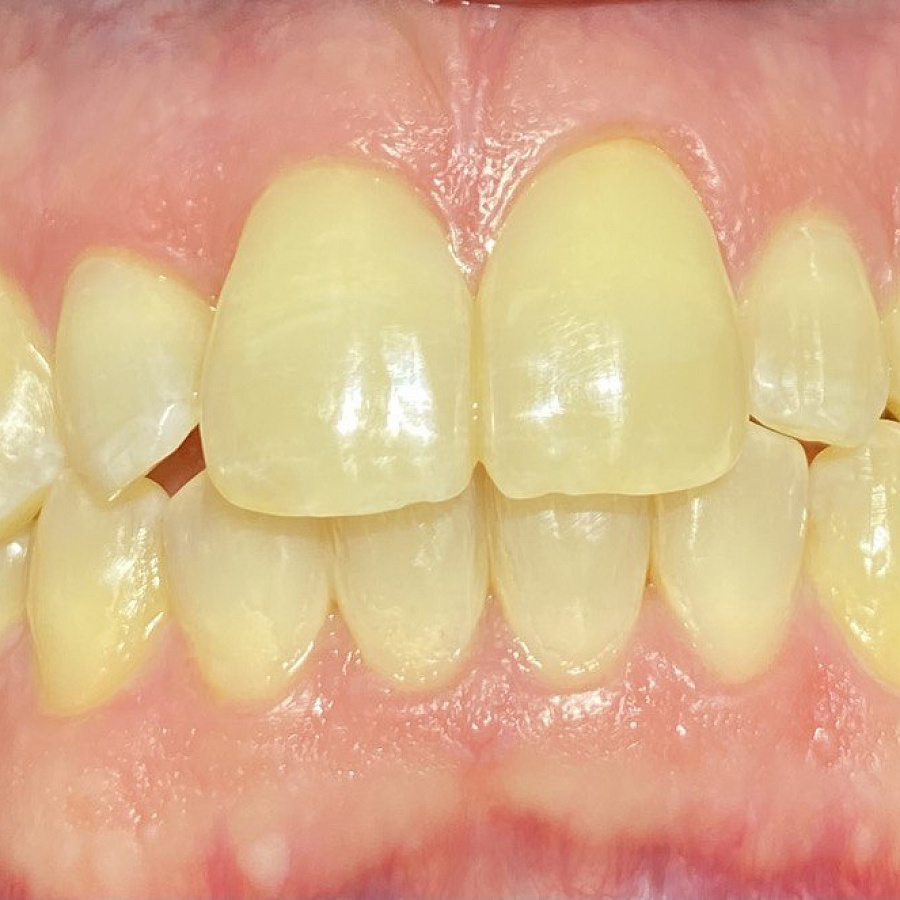

1. санация полости рта

2. ортодонтическое лечение с помощью элайнеров

3. восстановление плотных межзубных контактов с помощью ортопедических конструкций

4. виниры 12, 22 для удлинения резцов.

Ортодонтическое лечение с помощью элайнеров длилось 10 месяцев. Далее последовало протезирование и установка виниров.

Результат лечения